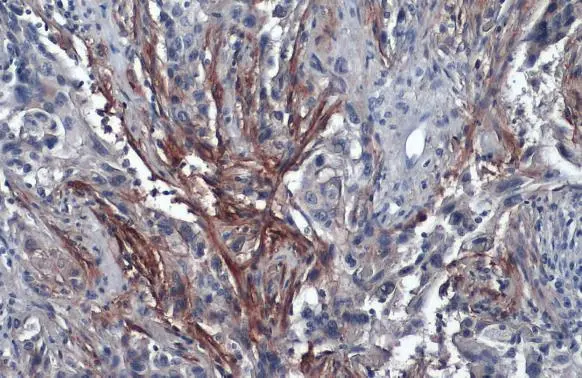

Anti-Carbonic Anhydrase IX antibody [GT12] used in IHC (Paraffin sections) (IHC-P). GTX70020

GTX70020 IHC-P Image

Immunohistochemical analysis of paraffin-embedded cervical CA tissue sections using anti-CAIX antibody [GT12] (GTX70020) at a dilution of 1:1000. The hypoxic regions of the tumor show positive CAIX staining.